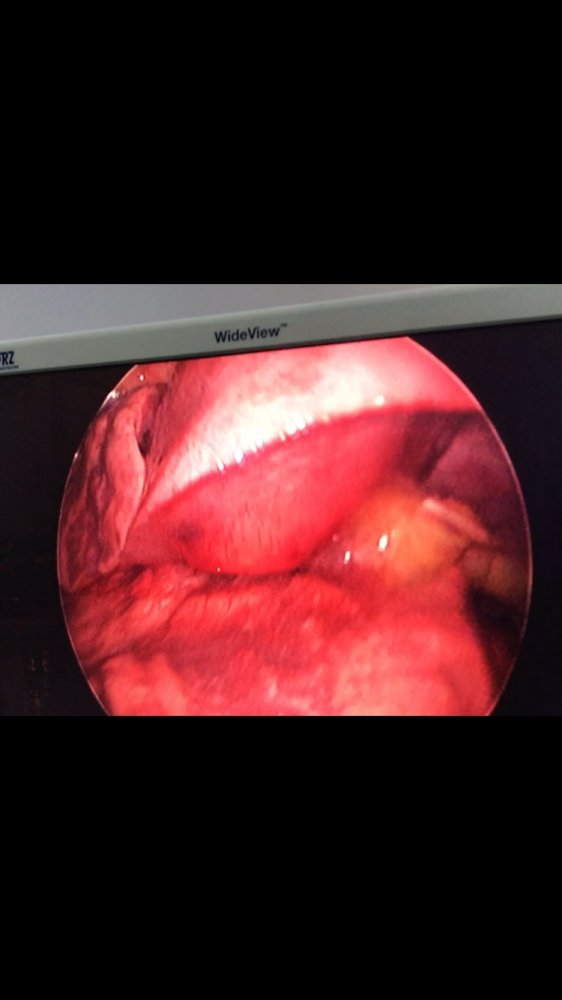

MediastinalTeratoma .Torokoskopik teratomanın eksiziyası

Daha bir çətin əməliyyat 8 yaşlı pasientdə döş boşluğunda törəmə- Ağciyərin orta payı üzərində böyük həcmli törəmə Teratoma. Torokoskopik törəmənin eksiziyası

Dr. Toğrul Ömərov